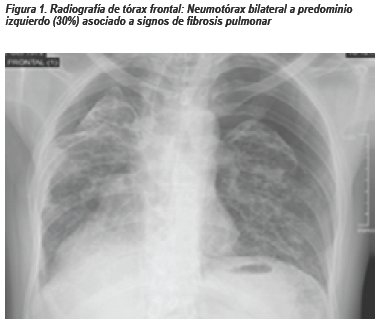

Paciente varón de 42 años natural y procedente de Lima, sin antecedentes médicos de importancia, con diagnóstico de Meduloblastoma Cerebeloso operado en el 2005 (craneotomía suboccipital izquierda + resección total de tumor), recibió adyuvancia con radioterapia y quimioterapia la cual consistió en 10 cursos de Carmustina (BCNU)yVincristina con regular tolerancia. Acude a control en Agosto 2016, refirió tiempo de enfermedad de 3 meses caracterizado por disnea a grandes esfuerzos la cual empeora súbitamente en la última semana. Al examen físico: paciente hemodinámicamente estable, taquicárdico, saturación de oxígeno 92%. La radiografía de tórax frontal muestra neumotórax bilateral a predominio izquierdo y signos sugestivos de fibrosis pulmonar.